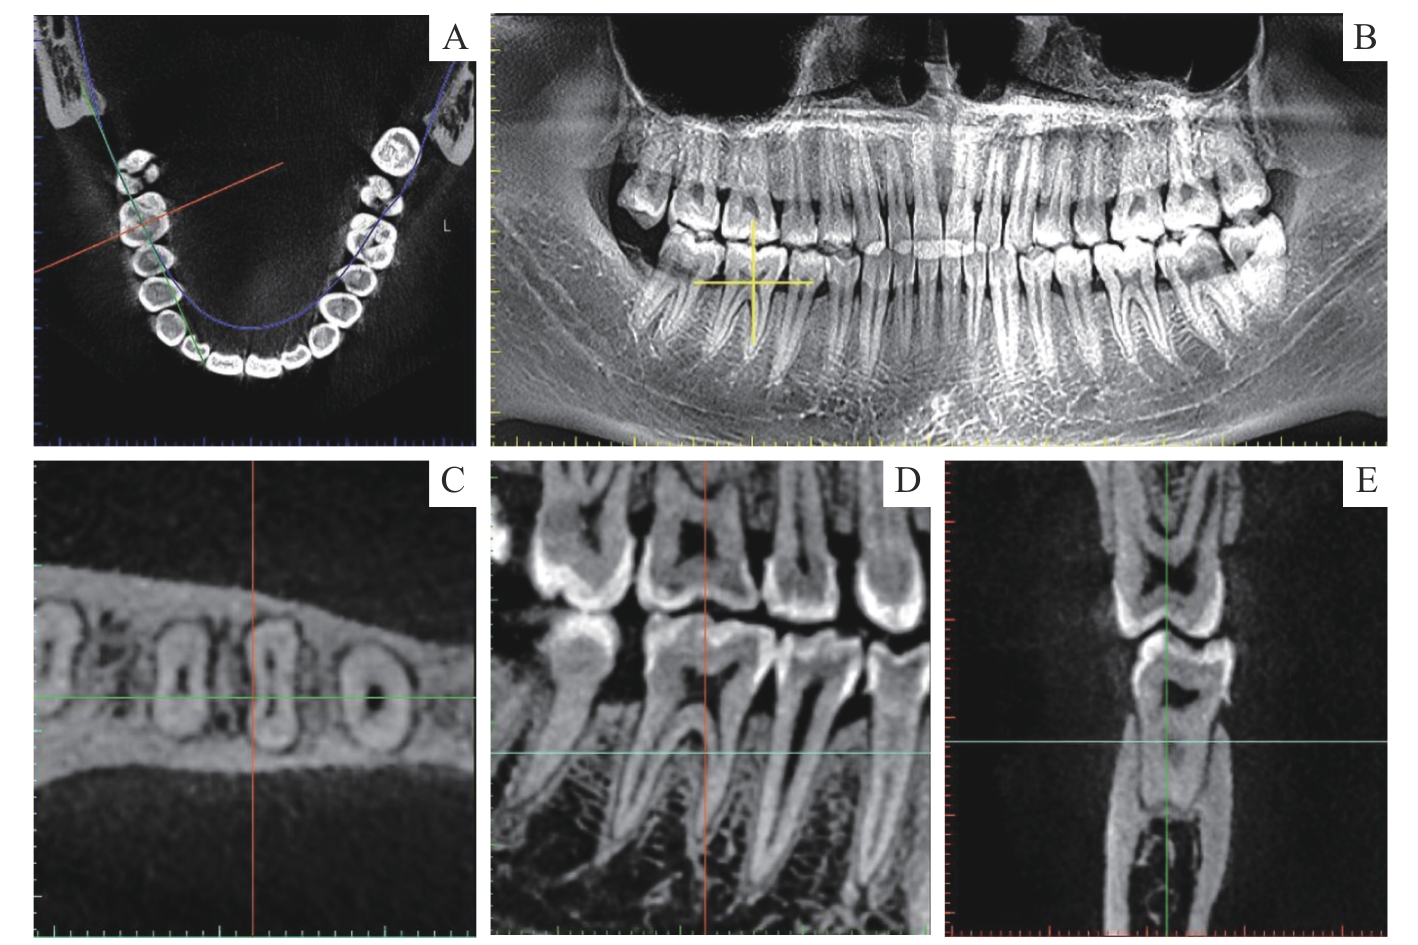

Cone-beam CT measurement of root canal diameter and taper for mandibular first molar

Objective ·To analyze the root canal diameter and taper of mandibular first molars using cone-beam CT (CBCT), investigate age-related changes in these parameters, and propose optimized clinical protocols for root canal preparation. Methods ·From October 2022 to October 2023, CBCT images of 240 healthy mandibular first molars (120 three-canal type cases and 120 four-canal type cases) were collected from patients aged 20‒59 years at the Stomatology Center, Haikou Affiliated Hospital of Central South University Xiangya School of Medicine. The three-canal type and the four-canal type samples were respectively divided into four age groups (20‒29, 30‒39, 40‒49, and 50‒59 years), with 30 cases in each group. Root canal length was measured, and buccolingual and mesiodistal diameters were recorded at four levels (coronal, middle, apical, and foramen). The tapers of the coronal 1/3, middle 1/3, and apical 1/3 segments were calculated in both buccolingual and mesiodistal directions. Differences among the age groups were compared. Results ·The buccolingual diameters of all root canals exceeded the corresponding mesiodistal diameters. At several levels of most root canals, the diameters in the <50-year-old groups were significantly larger than those in the 50‒59-year-old group (P<0.05). The buccolingual tapers exceeded the corresponding mesiodistal tapers in all root canals of mandibular first molars. The mean mesiodistal tapers in different age groups ranged from 0.07 to 0.34 in the coronal 1/3 segment, 0.03 to 0.09 in the middle 1/3 segment, and 0.05 to 0.11 in the apical 1/3 segment. At several levels of most root canals, the tapers in the <50-year-old groups were significantly larger than those in the 50‒59-year-old group (P<0.05). Conclusion ·Mandibular first molars exhibit age-related narrowing of root canal diameter and reduced taper in individuals aged ≥50 years. For initial apical file selection, #15 files are recommended for the distal canals in the three-canal type, while #10 files are advised for all other canals in the three-canal type and all canals in the four-canal type. For patients aged 50 years or older, the files for the distal canals in the three-canal type can be adjusted to #10, and the files for the mesiobuccal and distallingual canals in the four-canal type to #8. Regarding preparation taper, a 0.08-taper orifice opener is recommended for the coronal 1/3 segment. During mid-lower segment preparation, 0.04-taper master apical files are suggested for the mesiobuccal and mesiolingual canals in the three-canal type and the mesiolingual and distallingual canals in the four-canal type, 0.06-taper files for the distal canals in the three-canal type and the mesiobuccal canals in the four-canal type, and 0.08-taper files for the distobuccal canals in the four-canal type. Root canal obturation is recommended to be performed using vertical compaction with large-taper gutta-percha cones combined with bioceramic sealer.